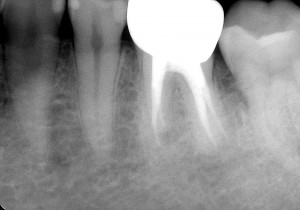

その後は経過も良く問題ありませんでしたので、被せ物の治療を行いました。

先日、いつもの3ヶ月毎の定期検診にお越しいただき、全体のチェックと共に根管治療部位のレントゲン写真も撮らせていただきました。

この10年症状も無く、もちろん新たなむし歯を作ることなく経過良好で過ごしていただいております。